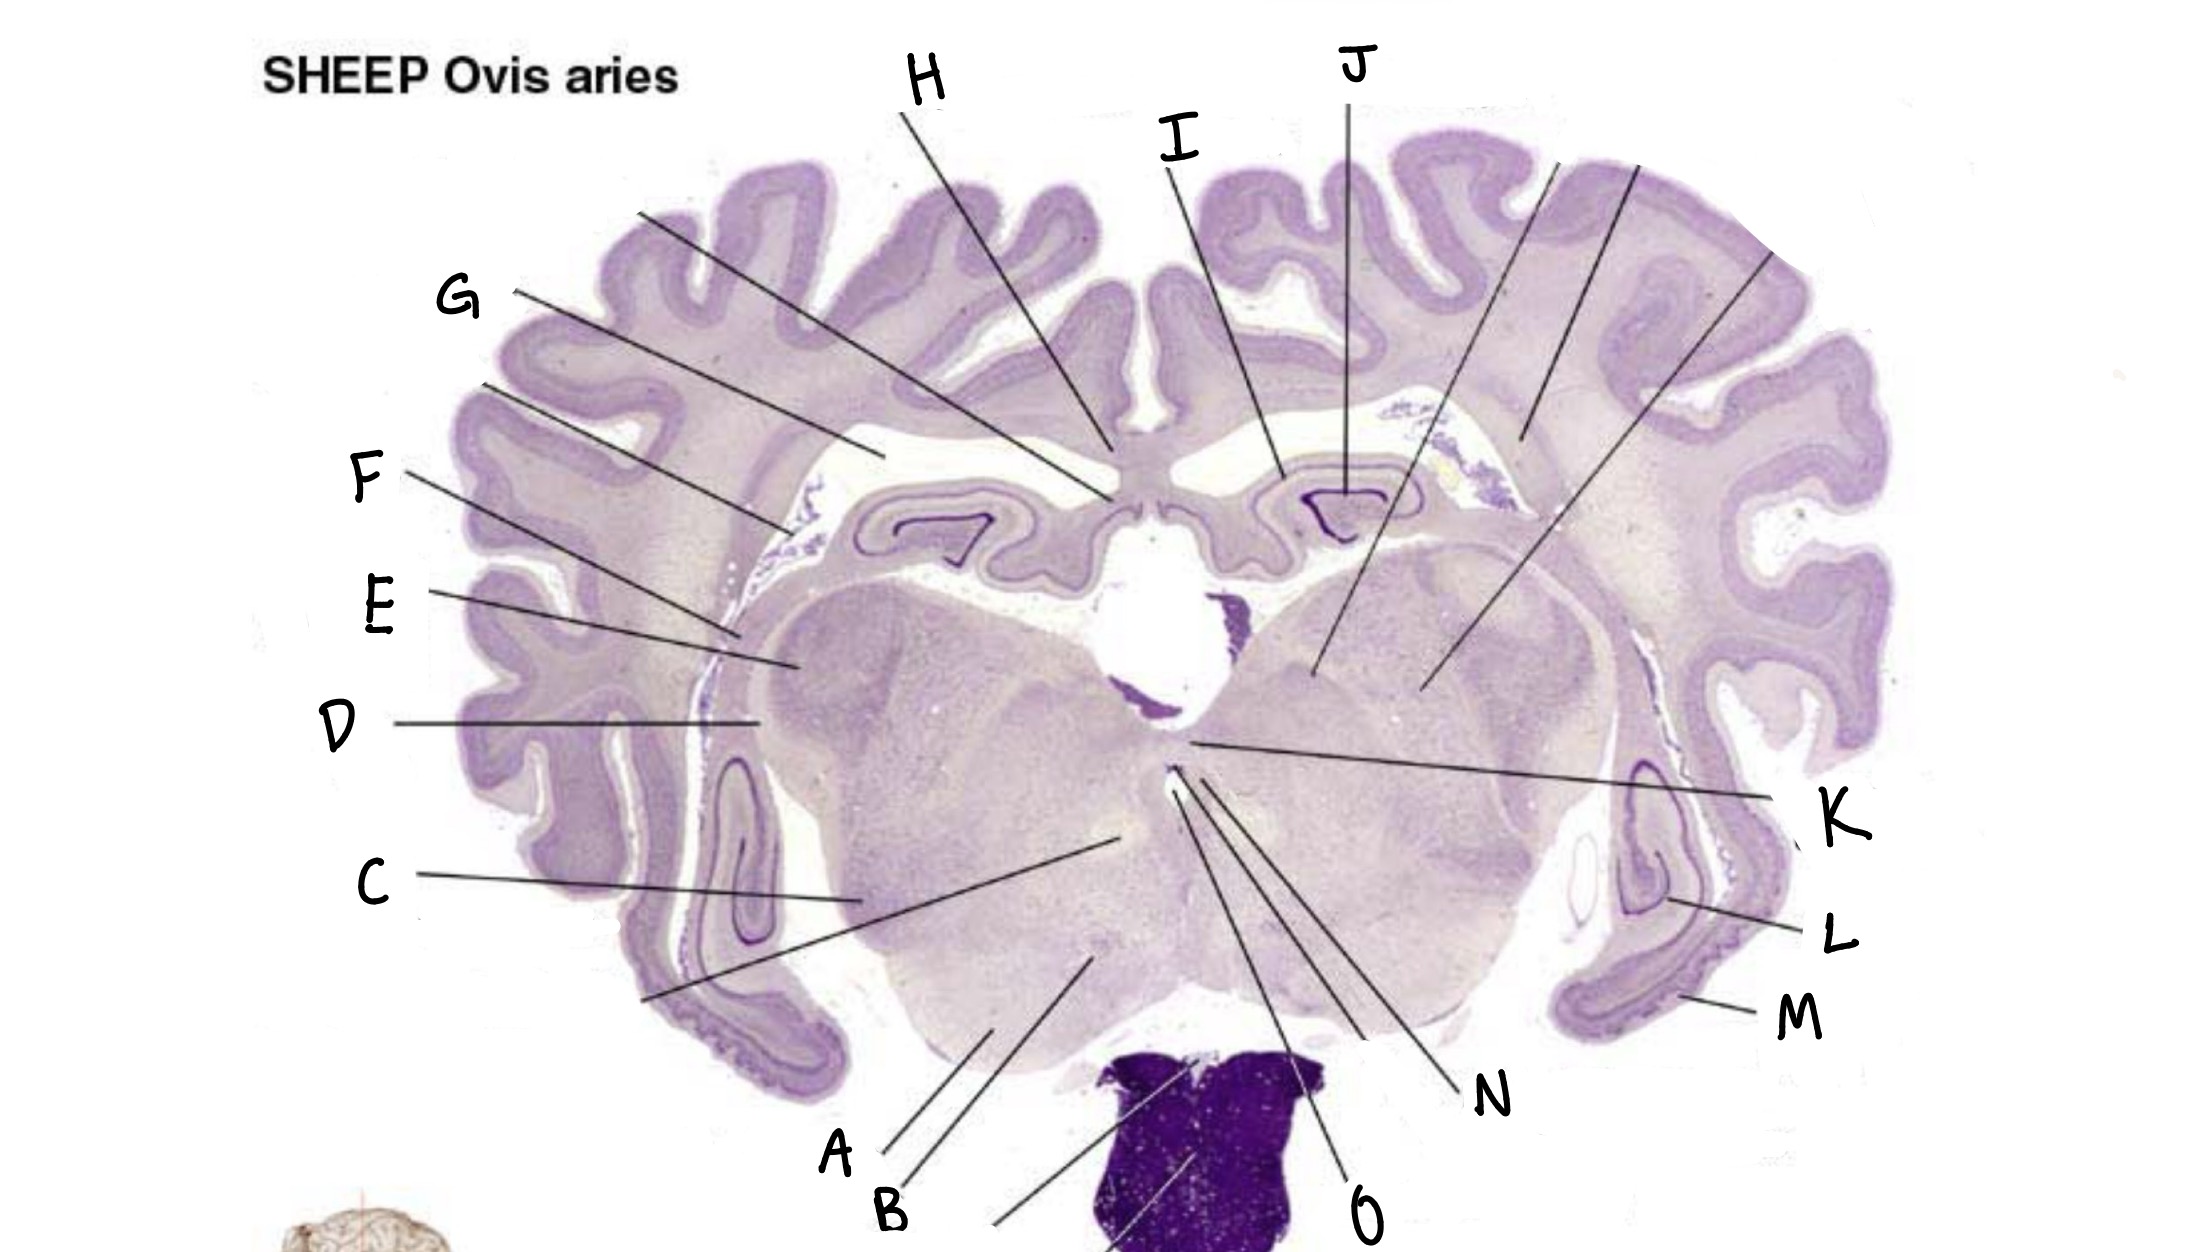

what is a

substantia nigra

what is b

red nucleus

what is c

medial geniculate nucleus

what is d

optic tract

what is e

lateral geniculate nucleus

what is f

fimbria

what is g

lateral ventricle

what is h

corpus callosum

what is i

ca3

what is J

dentate gyrus

what is k

posterior commissure

what is L

ca1

what is M

entorhinal cortex

what is n

periaqueductal grey

what is o

cerebral aqueduct